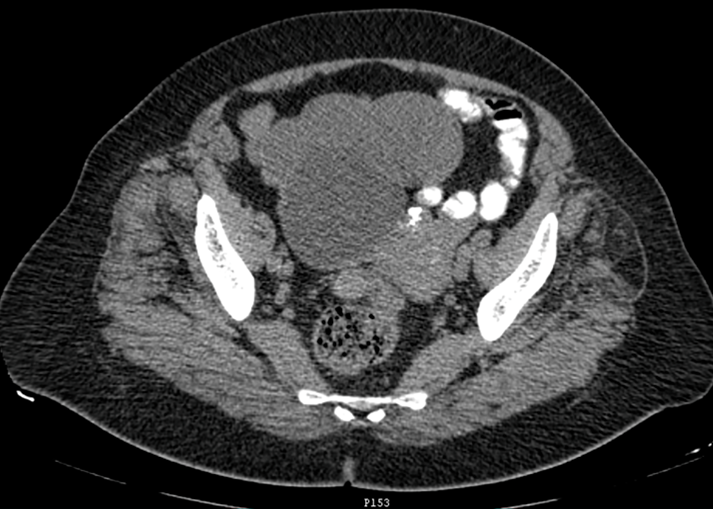

Figure 2: The upper part of the image shows a 14x5 cm lesion corresponding to the right uterine tube. The image was included and interpreted as a benign right adnexal tumor.

Diagnosed with a benign right adnexal tumor, a laparotomy was performed that revealed a 15x12 cm right ovarian tumor with a cystic component and a 14x5 cm right hydro salpinx with chocolate-like content through its wall (Figure 3). Total hysterectomy plus bilateral salpingo-oophorectomy was performed with a report of ovarian cystadenoma and endometroid adenocarcinoma of the right Fallopian tube. It showed dilation and the section revealed a nodular lesion, in its distal third, with a papillomatous appearance, white-yellowish, of a soft, sessile consistency, with endophytic growth of 2x1.5x.2cm (Figures 4, 5). The microscopic study showed a neoplasm of epithelial origin with a glandular, cribriform, papillary and even solid growth pattern that did not infiltrate the underlying capsule, (Figures 6, 7, 8).